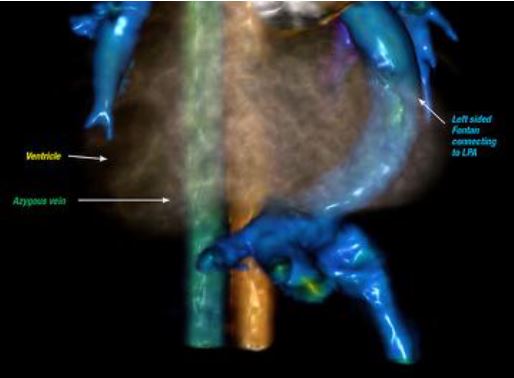

Interpreta mi Corazón… Lo que el radiologo debe reconocer en el seguimiento por imagen de las cardiopatias congenitas

Objetivos

• Facilitar la interpretación de las imágenes aplicando el análisis segmentario en el diagnóstico y seguimiento de las cardiopatías congénitas.

• Comparar la aplicación de cada una de las técnicas de imagen avanzada en el seguimiento de las CC.